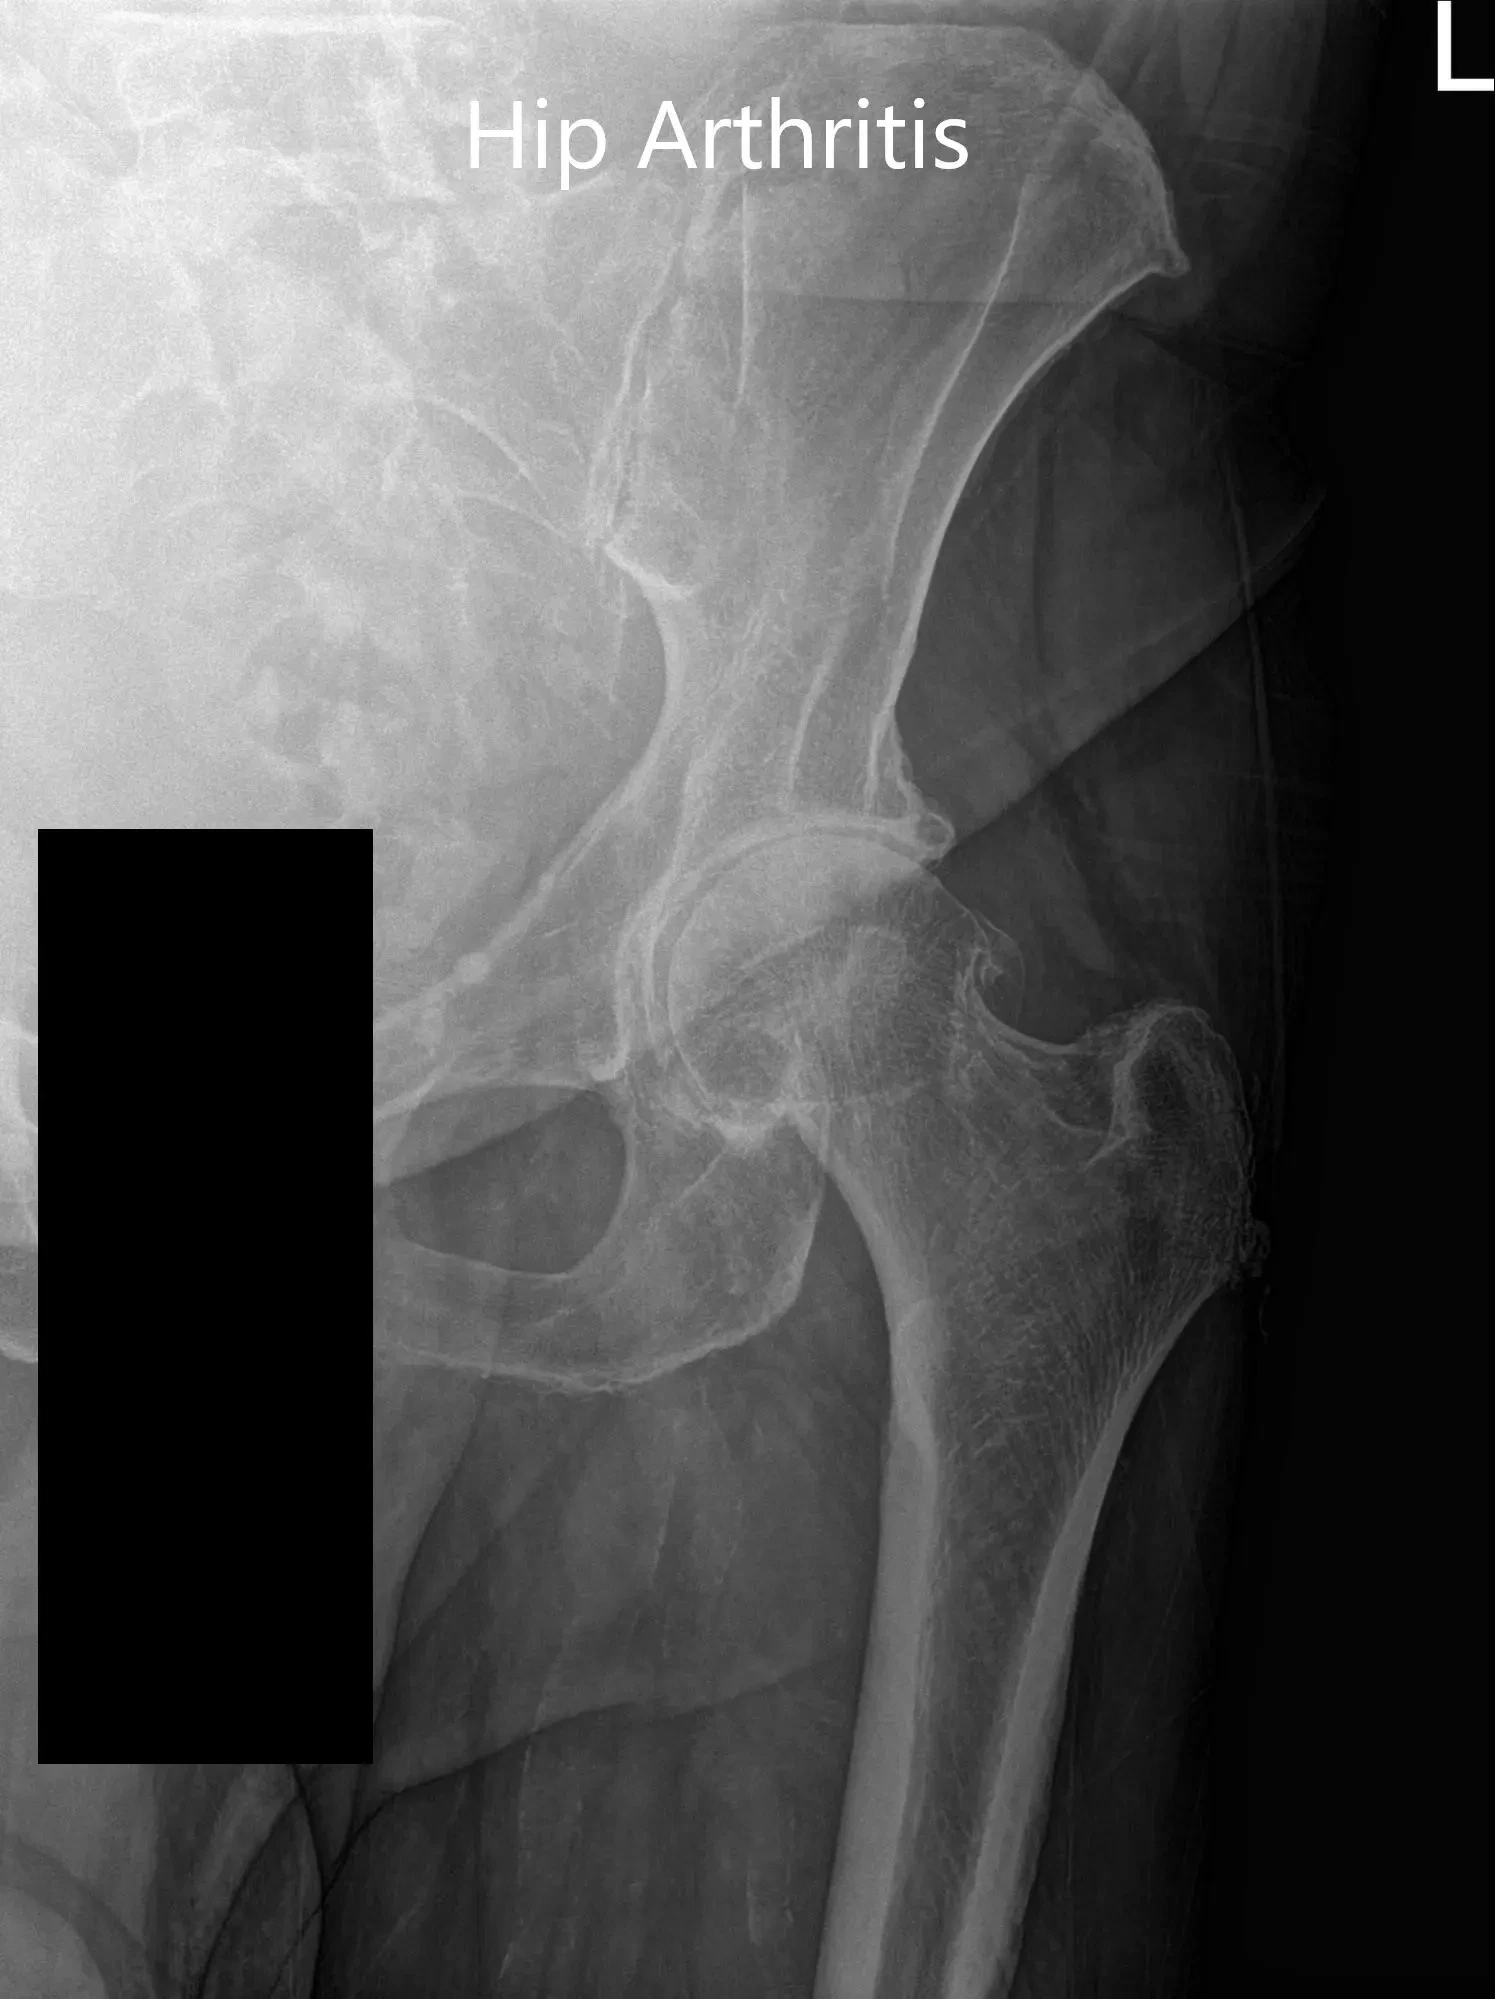

Imaging revealed severe osteoarthritis of the left hip. Considering, patients’ medical conditions and lifestyle limiting hip pain, she was advised left total hip replacement. Risks, benefits, and alternatives were discussed at length. She agreed to go ahead with the procedure.

Preoperative X-ray of the left hip showing AP and frog-legged lateral view